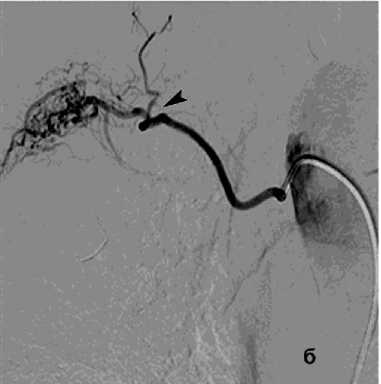

В 22 (14,7%) наблюдениях ЛК носило криптогенный характер, несмотря на проведённое обследование. Возможно, в ряде случаев ЛК было следствием курения [33, 34]. Однако это кровотечение может происходить в результате экстравазации крови в альвеолы и чаще возникает у взрослых обычно в возрасте до 30 лет. Клинический спектр идиопатического ЛГ варьирует от бессимптомных случаев до угрожающей жизни острой дыхательной недостаточности [9], одной из причин могут быть пороки развития сосудов лёгких (патологические соустья между двумя системами кровообращения) (рис. 2).

Рисунок 2. Ангиограмма правой БА: а – артерио-венозная мальформация стенки бронха базальных сегментов справа со сбросом в лёгочную артерию, ЛК1Б; б – состояние после эмболизация правой БА цилиндрическими эмболами (800 мкм)

Figure 2. Angiogram of the right bronchial artery (BA): a – arteriovenous malformation of the bronchial wall of the basal segments on the right with shunting into the pulmonary artery, PH grade 1B; б – status post embolization of the right BA with cylindrical embolic particles (800 μm)